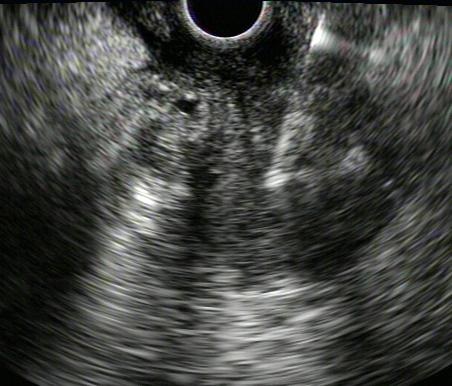

Endoscopic ultrasound (USE)Combines endoscopy and US

Diagnosis of the cause of BO

- Sensitivity 97%;

- Specificity 88%

Enables PAAF of neoplasias Operator dependent Not available in all centers Sedation